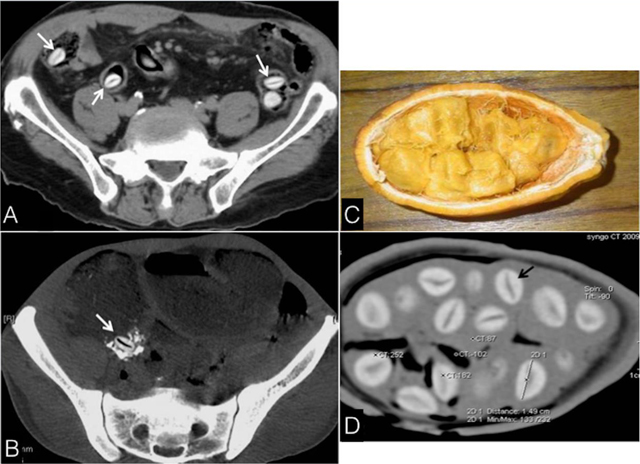

Figure 1

Axial CT images showing (A) SS seeds, incidentally found in the bowel (arrows), and (B) A seed impacted in the ileocecal valve (arrow), responsible for occlusion; Photograph (C) and CT (D) of SS; seed (dark arrow): maximum long diameter: 16 mm, high density of the shell (256 HU) and the midline linear hypodensity (92 HU).